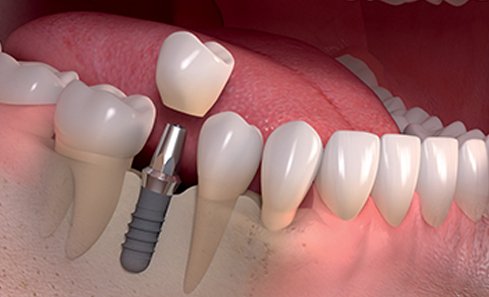

Implants are screw shaped that is placed in jawbone to replace a missing teeth. A crown is placed on this screw to look and function as the crown portion of the natural tooth. Dental implants are made majorly out of titanium material that suits the human body properly.